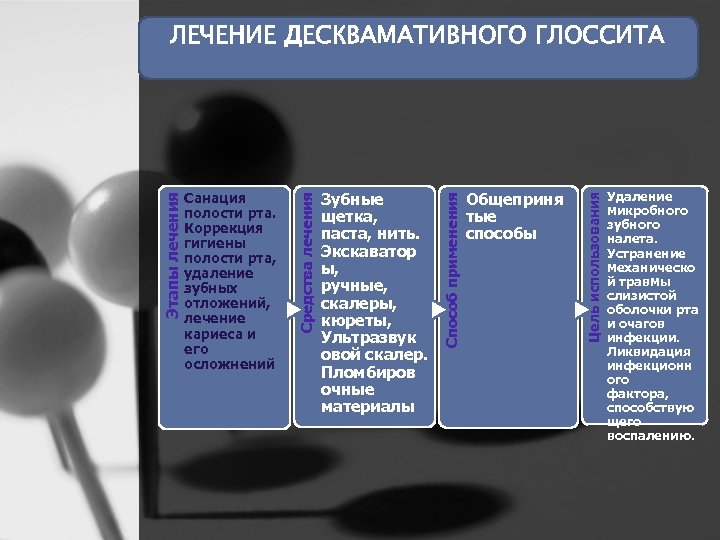

Общеприня тые способы Цель использования Зубные щетка, паста, нить. Экскаватор ы, ручные, скалеры, кюреты, Ультразвук овой скалер. Пломбиров очные материалы Способ применения Санация полости рта. Коррекция гигиены полости рта, удаление зубных отложений, лечение кариеса и его осложнений Средства лечения Этапы лечения ЛЕЧЕНИЕ ДЕСКВАМАТИВНОГО ГЛОССИТА Удаление микробного зубного налета. Устранение механическо й травмы слизистой оболочки рта и очагов инфекции. Ликвидация инфекционн ого фактора, способствую щего воспалению.